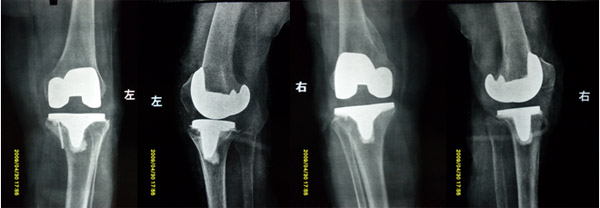

骨二科郭永良主任组织全体医师认真分析病例查找资料制定手术方案于2009.05.07在硬外麻醉下行双膝骨关节炎人工全膝关节置换术。对于左膝关节胫骨内侧平台骨缺损导致关节半脱位采取内侧平台植骨的方法恢复高度。手术顺利,双下肢恢复力线。术后10天患者恢复良好,关节可自主活动屈伸0°至70°。

术后X片示